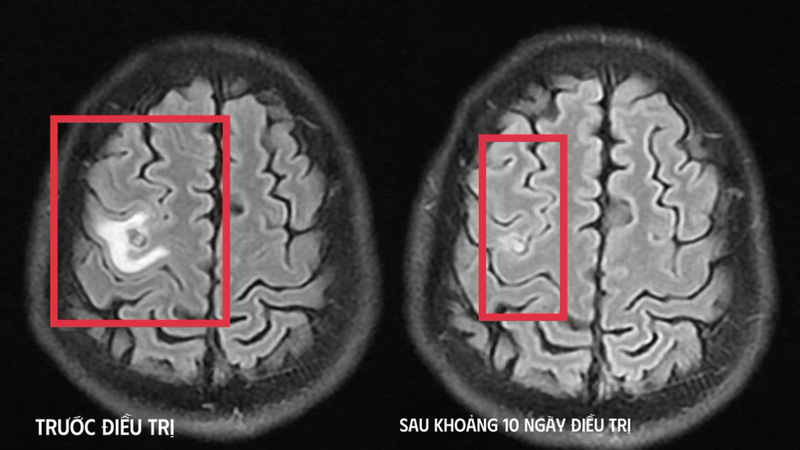

Qua chụp cộng hưởng từ (MRI) sọ não, các bác sĩ phát hiện một tổn thương dạng nang nhỏ tại thùy trán trái, kích thước khoảng 11 x 7 mm, kèm theo phù não nhẹ. Hình ảnh này không điển hình cho u não nguyên phát mà hướng nhiều hơn đến tổn thương do ký sinh trùng.

Sau khi xác định chính xác nguyên nhân, bệnh nhân được điều trị nội khoa theo phác đồ, kết hợp kiểm soát cơn co giật và theo dõi sát diễn tiến tổn thương não. Sau khoảng 10 ngày điều trị nội trú, các triệu chứng cải thiện rõ rệt: Bệnh nhân không còn co giật, hết đau đầu và cảm giác tê tay trái.